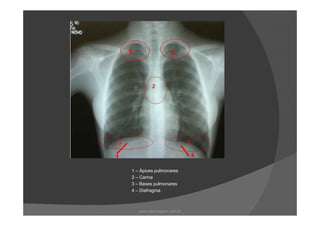

As regiões radiograficamente importantes do

pulmão são:

Ápice

Carina

Base

DiafragmaDiafragma

Tórax PA

1 – Ápices pulmonares

www.playmagem.com.br

2 - Carina

2 – Carina

3 – Bases pulmonares

4 – Diafragma

1 – Ápicespulmonares 2 – Carina 3 – Bases pulmonares 4 – Diafragma www.playmagem.com.br